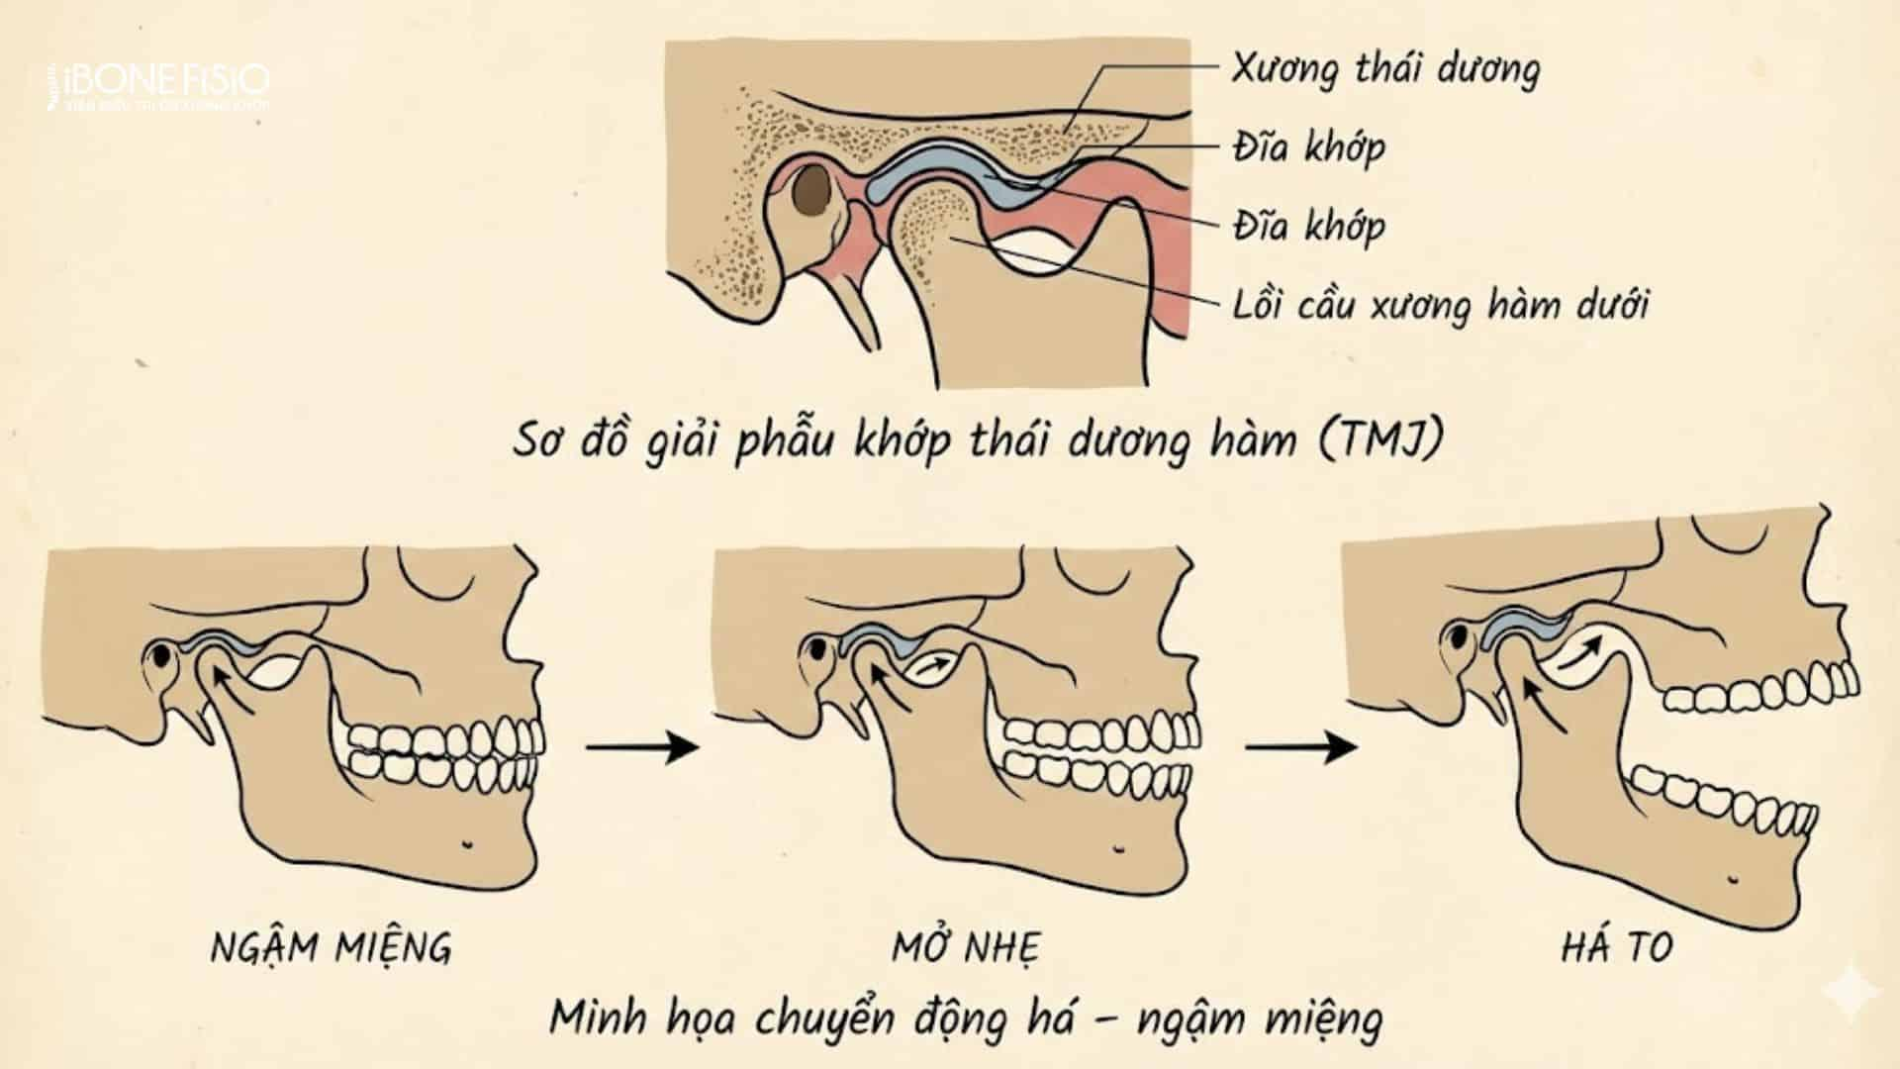

Ảnh 2: mức độ TMJ